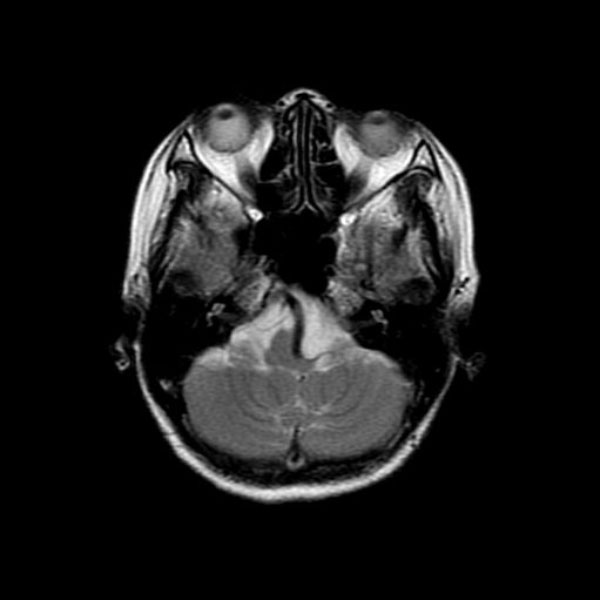

手術前

(MR1)